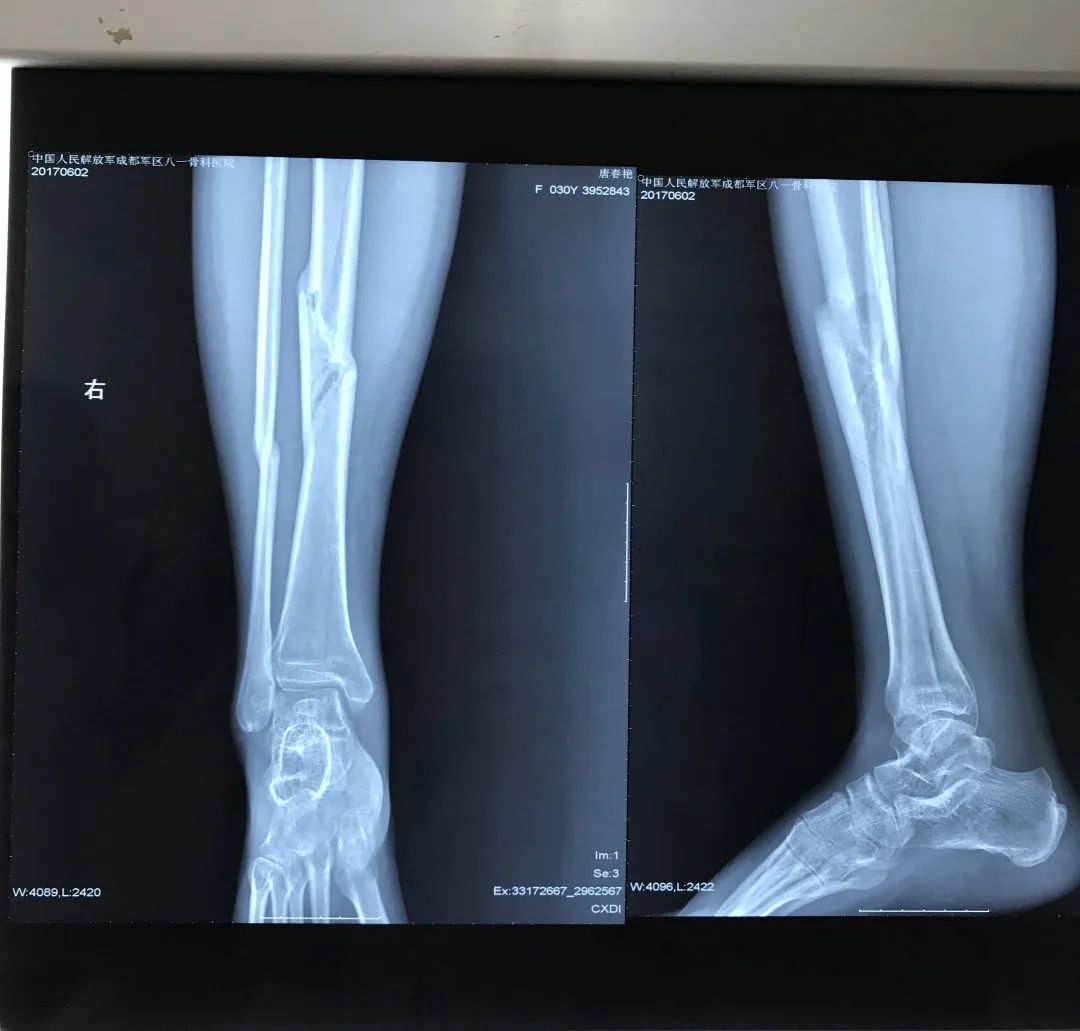

夫妻遭遇车祸,双双造成粉碎性骨折 八年前,唐女士夫妻俩曾经营着一家小商店,7月的一天,丈夫骑着摩托车带着她在前往门市的路上,被一辆小货车直接撞飞,然后俩人被重重的摔在了地上。“痛到麻木,我当时就想肯定完蛋了。”唐女士回忆到。 事故发生后,肇事司机立即拨打了急救120,唐女士夫妻随即被送到了就近的综合医院,经过全面检查,夫妻俩均被诊断为“胫腓骨粉碎性骨折”。“当时觉得特别有意思,我俩骨折的地方一模一样。”唐女士笑着说。 (唐女士第一次片子) 拒绝手术,转院寻求中医治疗 “当时医院建议我们手术,被我拒绝了。”唐女士回忆,由于害怕手术风险及后遗症,果断拒绝了手术治疗方案,而后通过多方了解,夫妻俩转院到了成都八一骨科医院。入院后,医院骨七科副主任医师叶丹丹作为唐女士的主治医生,对她的印象非常深刻。“当时考虑到患者的特殊性,科室专门调整了一个双人病房给唐女士夫妻。” 治疗上,叶丹丹医生采用“何天佐传统中医药正骨疗法”为唐女士夫妻进行手法复位,并辅以牵引疗法及外敷中药进行纯中医治疗。“效果非常好,8年过去了,我的腿没有任何后遗症!”准妈妈唐女士的脸上洋溢着幸福的笑容。 “医”心为患者,“医患”变朋友 八年前,不到30岁的唐女士与丈夫双双住院,家中两位老人不但要照顾两个病人,还要照顾家中两个小孩儿。唐女士看着老人们来回奔波,心里十分过意不去,住院治疗期间变得十分焦虑与不安。同为女性的叶丹丹医生看在眼里,尽己所能的为唐女士一家提供生活上的便利,并努力的帮助他缓解焦虑不安的不良情绪。“叶医生对我就像朋友一样,非常幸运能遇到这么好的医生。”唐女士说道。 住院治疗3个月后,唐女士及丈夫顺利出院。出院后,叶丹丹医生通过线上的方式,时刻为唐女士解疑达惑,居家康复应该怎么做?生活上有哪些注意事项?等等。八年时间里,俩人的话题也从医疗问题延伸到了各自的家庭与生活,也从“医患关系”变成了朋友。 “你信任我,我治愈你”最好的医患关系一定是双向奔赴,朝着同一个目标作出各自的努力,共同完成对疾病的治愈以及对健康和生命的守护。这些年,叶丹丹医生一心为患者着想,“医患关系”变朋友的案例不在少数,有时候患者也会送来锦旗、感谢信等,叶医生表示这是患者对她工作的认可和肯定,同时也是对她的一种鞭策,她将继续用专业的技术为每位患者提供更加优质的服务。